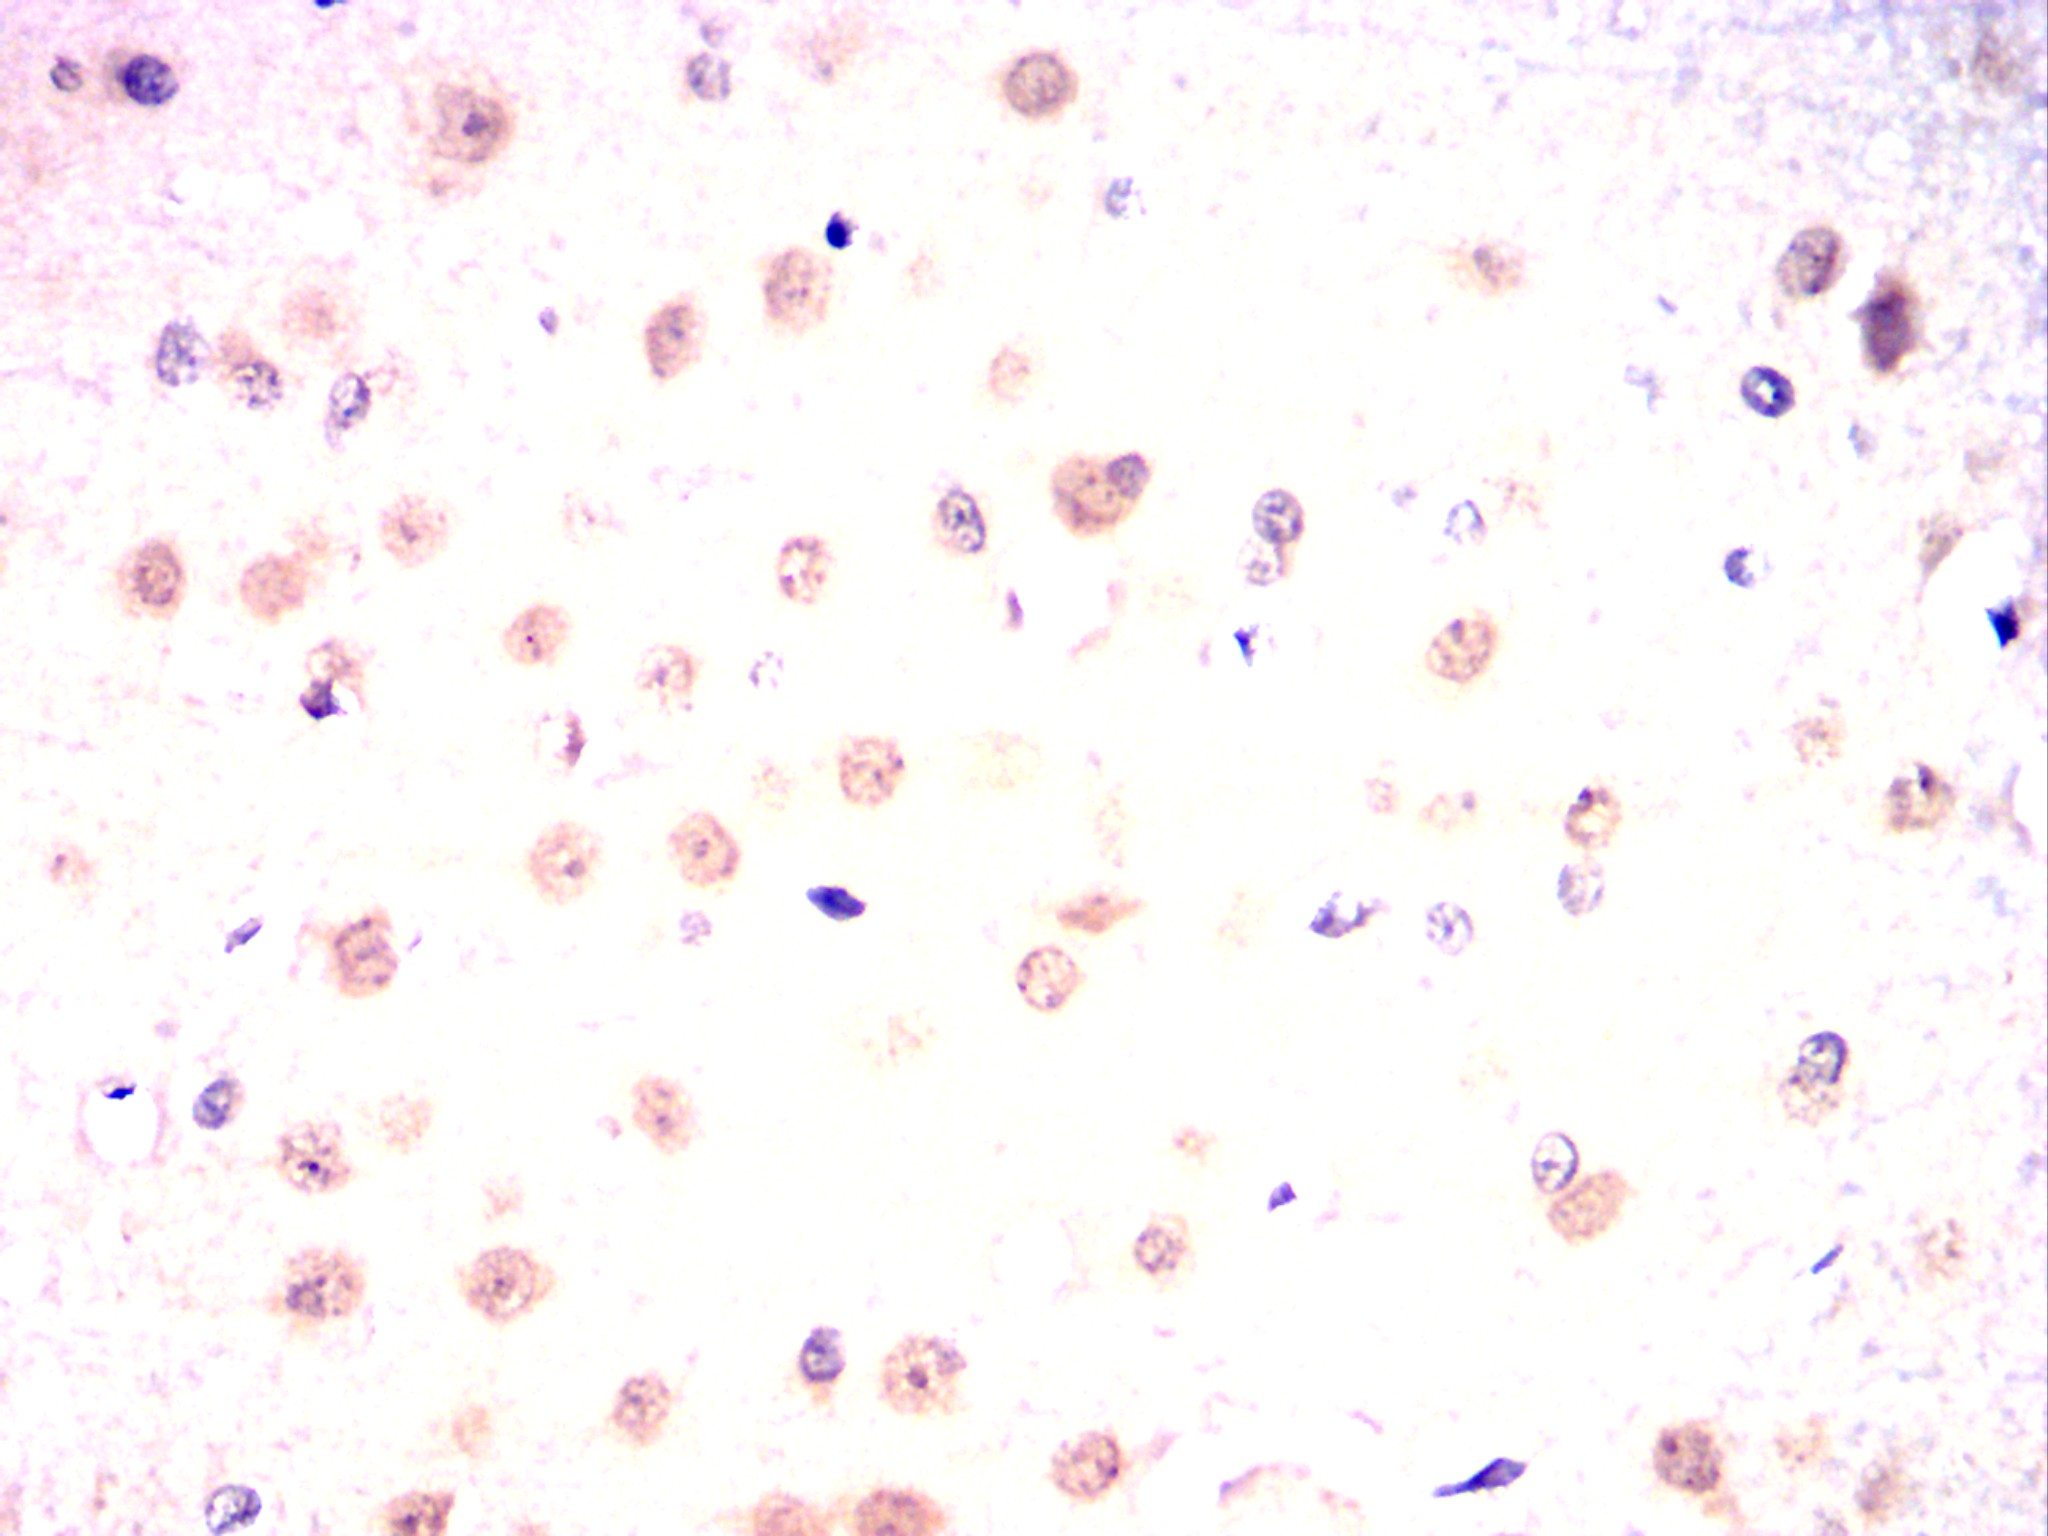

Immunohistochemical analysis of paraffin-embedded Rat brain using OTX2 mouse mAb with DAB staining.